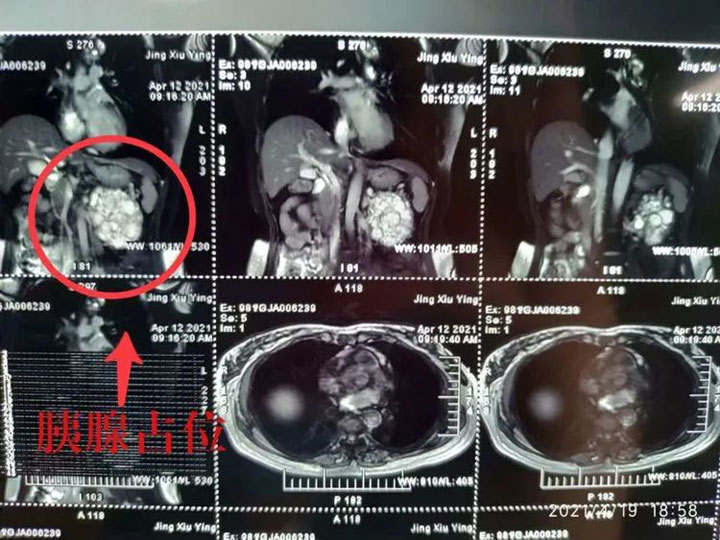

患者金女士,一月前在体检中发现了胰尾部占位。经朋友推荐,求诊于广济医院普外科顾冕主任。顾主任立即为其完善检查,触诊腹壁一10*6*10大小包块,CT提示:胰腺尾部占位,考虑为浆液性囊腺瘤,诊断为胰腺占位性病变。综合各项检查结果,顾主任团队为金女士拟定了“腹腔镜下根治性胰体尾切除术联合脾切除术”的治疗方案。经过家人的一致讨论,决定选择在广济医院普外科由顾主任为金女士主刀。

随后经全麻为其行腹腔镜下根治性胰体尾切除术联合脾切除术,顾冕主任技术娴熟,选择患者疼痛神经少的位置做切口入路,进入腹腔后逐步游离组织、韧带、结扎目标血管,从下缘游离到上缘,通过胰后隧道悬挂预阻断,离断胰腺组织、缝合、放置引流管.....一气呵成,3个小时后,手术顺利结束,患者安返病房。

术后第二天,金女士已经可以下床活动。“患者术后引流液十分清亮,量也比较少,再观察观察就可以拔除引流管了”,普外科代坤主任说道,“胰腺手术作为普外科最大的手术,堪称‘皇冠上的明珠’,是三级医院必备的技术病种,也是衡量普外科医生技术成熟水平的标志。作为腹膜后器官,胰腺毗邻脾脏、胃,被十二指肠环形包围,周围的血管神经十分丰富,顾主任技艺精湛,精细精准精确的解剖层面,胰腺断面几乎没有出血。腹腔镜下操作对手术医生技术要求很高,对患者恢复十分有利,临床应用十分广泛。”